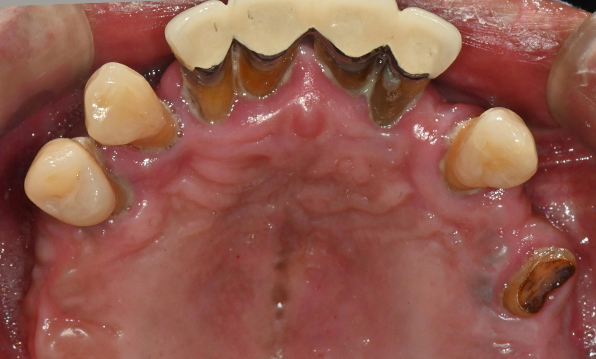

잇몸뼈가 얇은 상태

-

잇몸뼈 충분히 이식 후 임플란트 식립

성공을 위한 노하우, 잇몸뼈 재건 기술

전체 임플란트를 해야하는 환자들은

대부분 고령의 환자들로 오랜 틀니 사용

또는 노화로 인해 치조골이

거의 남아있지 않는 경우가 많습니다.

이 때, 치조골 이식을 병행하여 잇몸뼈 재건 후 안정적인 임플란트 식립을 하고 있습니다.

치료기간 : 2021.04.12~2021.09.15